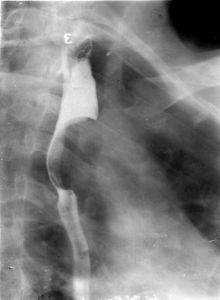

X線食管鋇餐檢查:是本病的主要診斷方法,結合臨床表現,往往可以一次造影確診。腔內充盈缺損是主要表現,缺損呈圓形或橢圓形,邊緣光滑銳利,與正常食管分界清楚。